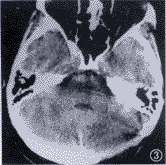

例3 患者44岁, 因双侧卵巢浆液性乳头状囊腺癌,于1993年4月6日接受子宫、双侧附件、大网膜切除和阑尾切除术。术后残留癌直径>2cm。临床病理分期为Ⅲc期,G2。术后采用PAC方案化疗9个疗程。化疗后行二次探查术和盆腔淋巴结清扫术,又行化疗3个疗程。第1次手术后临床无病变期26个月,1993年8月可疑盆腔复发,给予顺铂、吡喃阿霉素和环磷酰胺方案化疗3个疗程。第1次术后38个月因卵巢癌结肠转移(直径2.5cm),行第3次手术,切除部分乙状结肠和直肠。术后残留癌直径<2cm。化疗方案选择泰素和卡铂治疗6个疗程。此后定期随诊。1997年9月患者因剧烈头痛渐进性加重3周,行CT检查,发现小脑转移灶(图1)。于第1次术后53个月,行开颅手术切除小脑延髓池肿瘤6cm×6cm×5cm,病理报告为卵巢癌脑转移(图2)。术后采用威猛26 和甲基环己亚硝脲方案化疗11个疗程(剂量同例2,间隔6周1次)。化疗第1,2疗程之间患者接受了全颅照射,化疗半年和1年后再次行脑CT检查,无转移灶存在(图3)。脑转移后存活19个月。

图3 脑CT检查显示,颅内无转移病灶